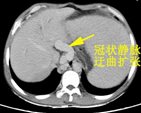

术后1月CT

血栓陈旧无法完全溶解,但因选择性贲周血管离断术保留了冠状静脉,门静脉血流可以通过食管下端交通支返流,无腹水等并发症发生。